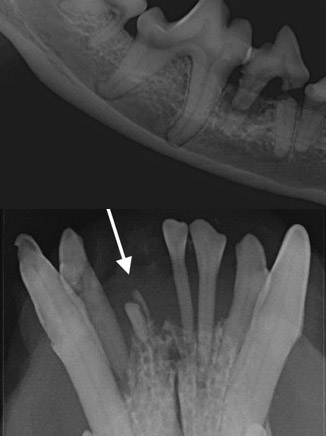

Maitohampaat

Pennuilla esiintyy myös usein ongelmia maitohampaiden kanssa. Maitohampaat saattavat jäädä irtoamatta itsestään, jolloin ne on syytä poistaa. Maitohammasta ei ole tarkoitettu jäämään suuhun ja siksi se ajan myötä tulehtuu helposti. Myös monet purentaviat edellyttävät maitohampaiden poistoa tieltä mahdollistamaan pysyvien hampaiden kasvun oikeaan paikkaan. Maitohampaita poistettaessa pysyvät hampaat ovat vielä hyvin ohutkuorisia ja herkkiä vaurioitumaan varomattomassa poistossa. Tämän vuoksi on aina syytä röntgenkuvata alue ennen maitokulmahampaan poistoa, jotta nähdään puhkeamattoman pysyvän hampaan sijainti maitohampaaseen nähden. Maitohampaan juuri on monesti myös osin jo syöpynyt ja heikentynyt. Röntgenkuvasta voidaan ennakoida miten poisto kannattaa suorittaa, jotta juuri saadaan luotettavasti kokonaan poistettua.